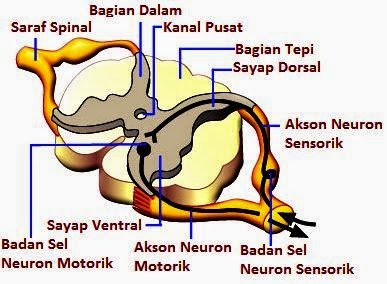

Sistem Saraf Pada Manusia Sistem Saraf Pusat Sistem

Sistem Saraf Pada Manusia Sistem Saraf Pusat Sistem